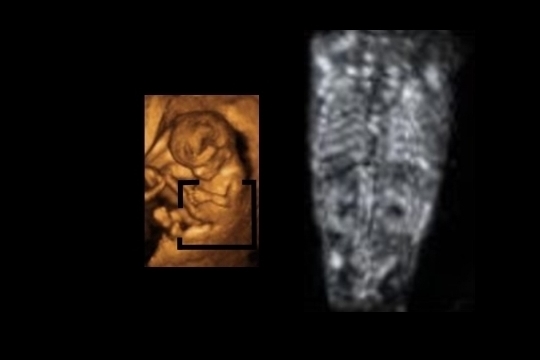

Corte axial o transverso